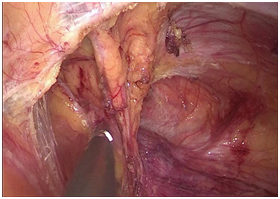

腹腔镜术中照片

腹腔镜是一种带有微型摄像头的手术器械,腹腔镜手术就是利用腹腔镜及其相关器械进行的手术:使用冷光源提供照明,将腹腔镜镜头(直径为5—10mm)插入腹腔内,运用数字摄像技术将拍摄到的图像通过光导纤维传导至后级信号处理系统,并且实时显示在专用监视器上。手术医生通过监视器屏幕上所显示的图像,运用特殊的腹腔镜手术器械进行手术。

传统的开腹手术需要在腹部切开一个约20—25cm大小的切口,然后进行病灶切除。而腹腔镜手术只需在皮肤表面做3—5个直径约0.5—1cm小孔,腹壁上没有传统开腹手术的大切口,手术创伤小、术后疼痛少、恢复快,故被称为微创手术。